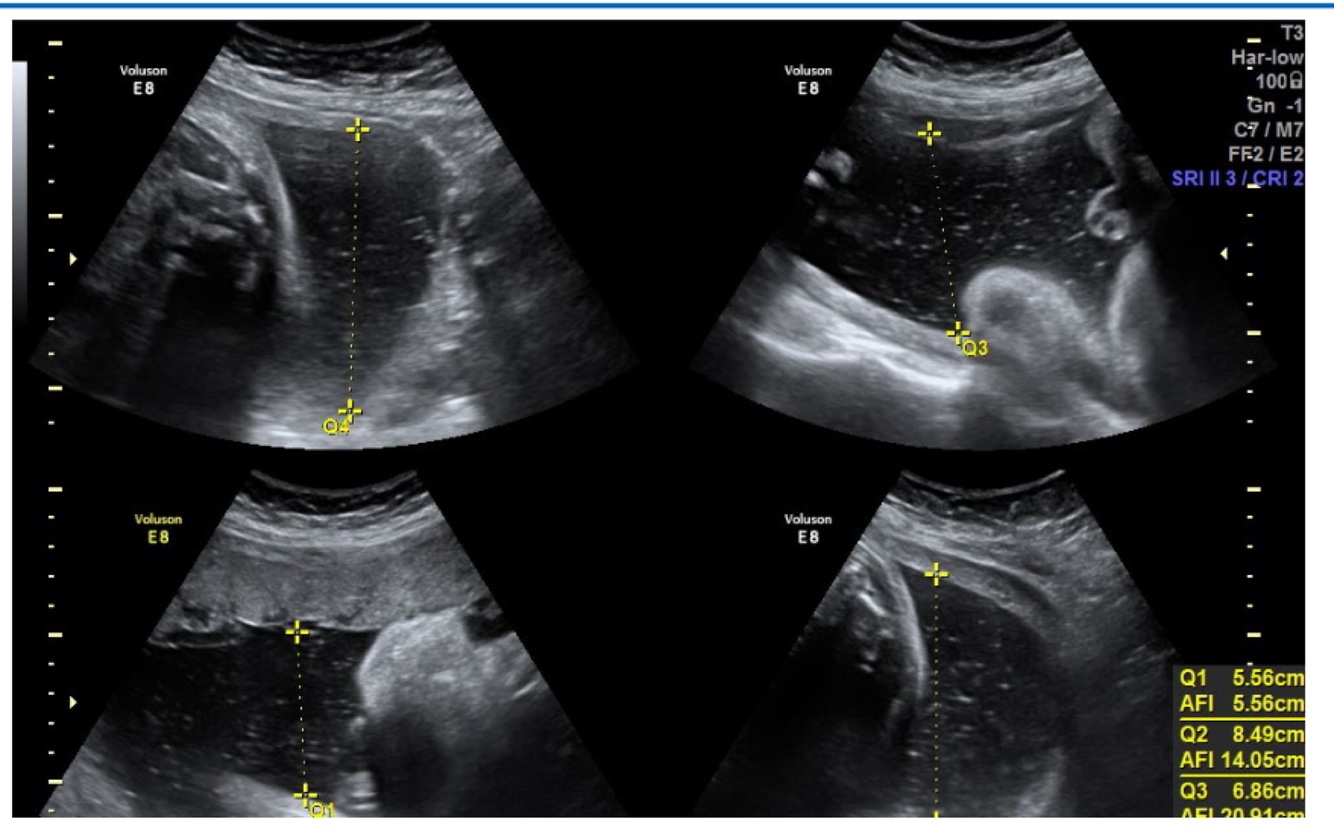

Q

What does this image demonstrate?

A

Polyhydramnios, AFI is >25cm